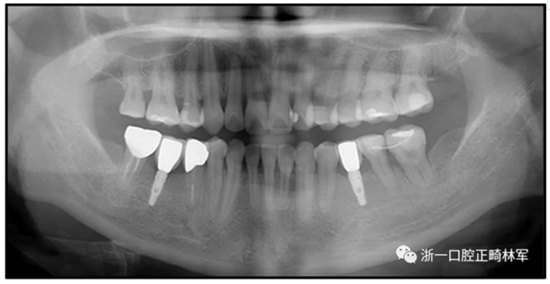

36歲;女性;尋求下頜左后方區(qū)域間隙管理的建議(圖1和圖2),通過(guò)治療獲得了良好的牙頜面效果(圖3和圖4)。她被診斷患有骨性I類(lèi)和代償性牙性II類(lèi)錯(cuò)合畸形,并且上頜左側(cè)尖牙缺失(圖1和2)。大約七年前,由于不可修復(fù)的齲齒,拔除了下頜左側(cè)第一和第二磨牙(圖5)。37相鄰的第三磨牙向近中移動(dòng)并傾斜入間隙,導(dǎo)致無(wú)牙頜間隙減小至約14 mm(圖2和圖5)。臨床和影像學(xué)評(píng)估顯示多發(fā)性齲損和在下頜右側(cè)567處有一不良的固定橋修復(fù)體(圖1和5)。此外,下頜左中切牙缺失,造成下頜中線(xiàn)向左側(cè)偏移約3 mm(圖1和圖2)?;颊咦栽V,她的右上第一前磨牙和左上尖牙在13歲時(shí)由其家庭牙醫(yī)拔除,因?yàn)樗鼈儽蛔枞筋a側(cè)萌出(圖1)。上頜第二磨牙缺失(未知病因),并且相鄰的第三磨牙已經(jīng)轉(zhuǎn)移到第二磨牙間隙中。如補(bǔ)充材料所示,美國(guó)正畸學(xué)差異指數(shù)DI是28分。種植體部位(下頜左側(cè)和右側(cè)第一磨牙)由于復(fù)雜性得到額外4分(補(bǔ)充材料)。

總之,這種復(fù)合錯(cuò)合畸形是一個(gè)很?chē)?yán)重的問(wèn)題,需要進(jìn)行認(rèn)真的多學(xué)科序列治療。治療后X光片(圖6)和重疊頭影測(cè)量圖(圖7)記錄了跨學(xué)科治療結(jié)果。

圖5. 治療前的側(cè)位片(上圖)和全景(下圖)的X光片